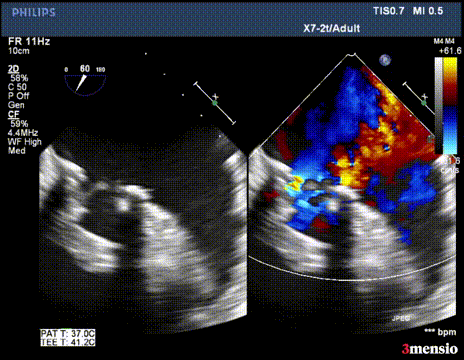

二尖瓣反流消失,跨瓣压差3mmHg;左室流出道血流速度正常